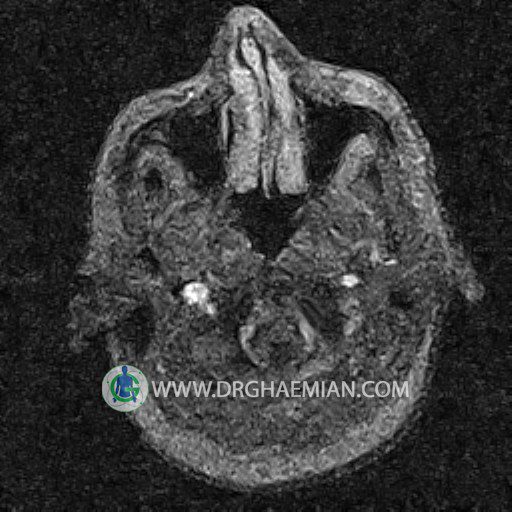

ام آر وی یک روش تصویربرداری دقیق و غیر تهاجمی است که برای معاینه ورید های بدن و ارزیابی سلامت رگ ها استفاده می شود. ورید ها خون را از اعضای بدن به قلب باز می گرداند تا دوباره اکسیژن و مواد مغذی به خون داده شود. ام آر وی جریان خون را ارزیابی و موارد غیرعادی مضر مانند لخته های خونی را شناسایی می کند. در این کیس ترومبوز دیواری مغز در سینوس عرضی راست و ترمبوز جزئی در سینوس عرضی چپ دیده می شود.

Images of the venous cranial vessels demonstrates a superior sagittal sinus of normal caliber with normal arrangement of draining superficial cerebral veins.

The great cerebral vein Galen inferior sagittal , straight sinus and left sigmoid sinus appear normal.

The right sigmoid sinus present a normal caliber.

The other evaluable deep cerebral veins , basal and labbe are normally developed and patent.

The other evaluable portions of the neurocranium show no abnormalities.

– Narrowing of left transverse sinus with filling defect & inthimal irregularity

suggestive for partial thrombosis

– Inthimal irregularity in anterior wall of right transverse sinus suggestive for mural thrombosis

are seen